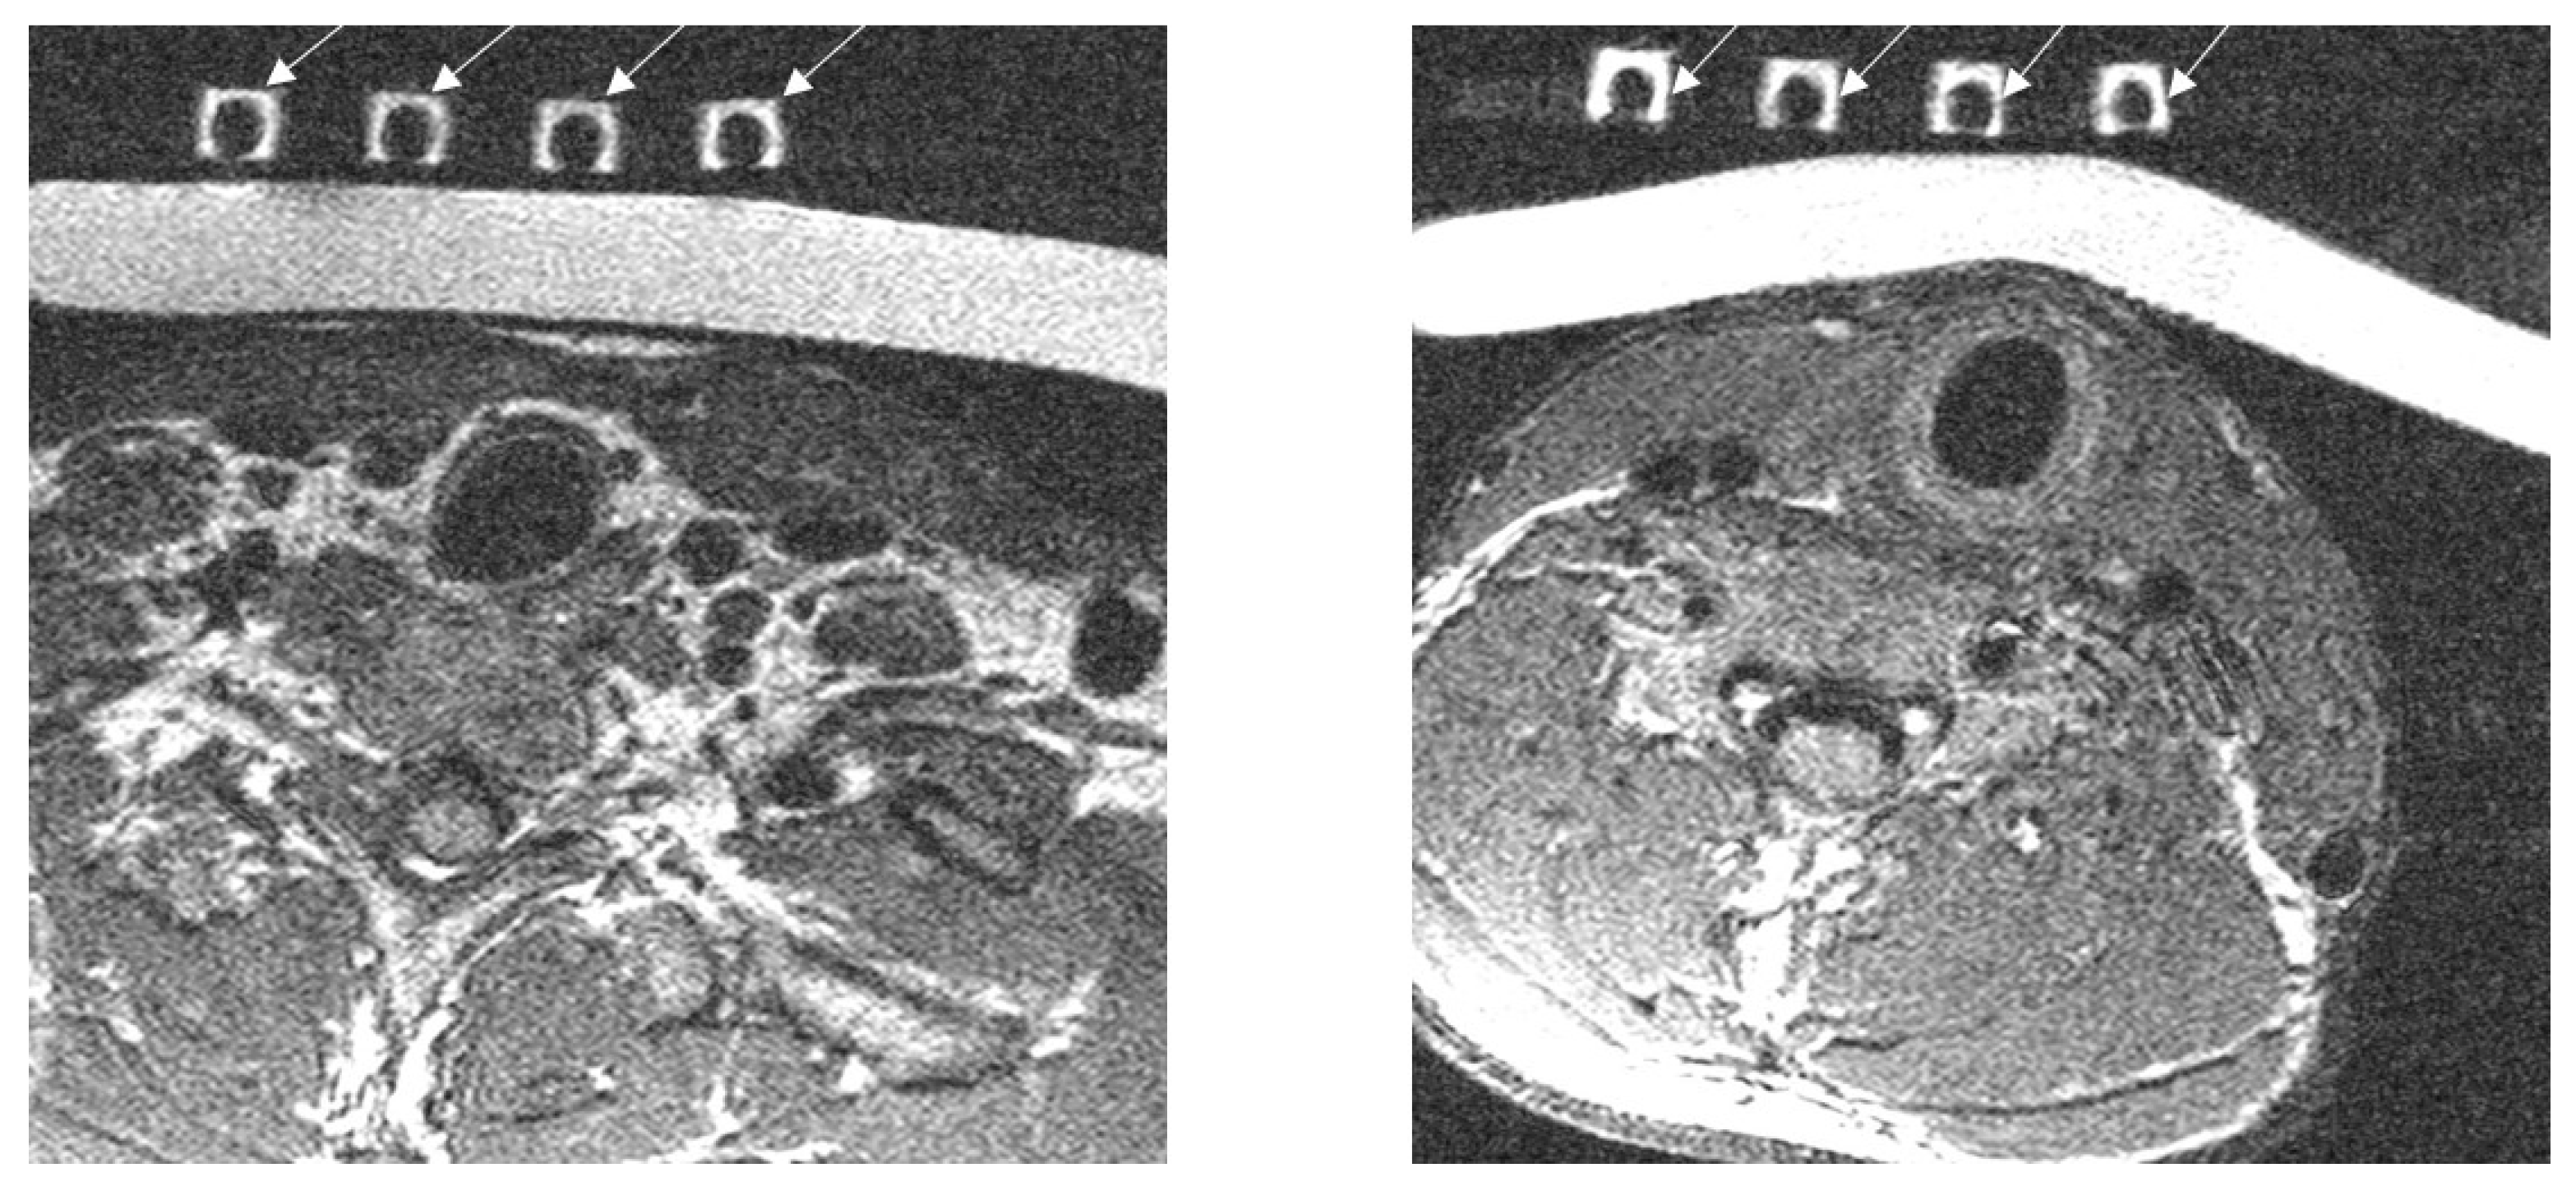

2.5. Experimental Imaging of the Human Neck

3.3. Imaging of the Neck